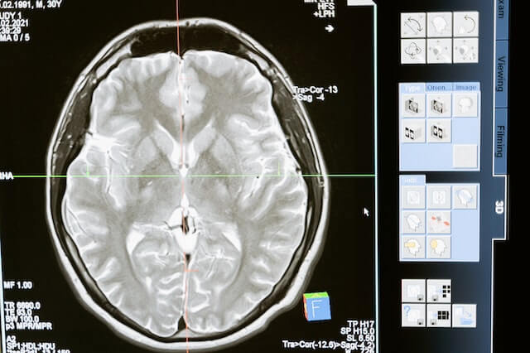

뇌졸증은 뇌의 혈류가 중단되어 뇌세포가 손상되는 질환으로, 매우 심각한 건강 문제이자 사망 원인 중 하나입니다. 뇌졸증을 예방하기 위해서는 원인을 정확히 이해하고 건강한 삶의 지침을 따르는 것이 중요합니다. 뇌졸증은 크게 두 가지 유형으로 나뉩니다. 허혈성 뇌졸중은 혈관의 혈전이나 혈전이 원인이고, 출혈성 뇌졸중은 혈관이 파열되어 뇌에 출혈이 생기는 것입니다. 이 두 가지 유형 모두 고혈압, 당뇨병, 흡연, 과체중 등의 원인이 있는 경우 발생할 확률이 높아집니다. 뇌졸증 예방을 위한 건강한 삶의 지침은 다음과 같습니다. 첫째, 정기적인 건강검진을 통해 고혈압, 당뇨병 등의 질병을 조기 발견하고 관리하세요. 특히 중년 이상의 경우, 고혈압의 발병률이 높아지므로 정기적인 검사가 필요합니다. 둘째, 건강한 식습관은 뇌졸증 예방에 중요한 역할을 합니다. 나트륨 섭취를 줄이고, 식이섬유와 불포화지방산이 풍부한 과실, 채소, 견과류 등을 섭취해야 합니다. 셋째, 꾸준한 운동은 뇌졸증 발생 위험을 낮춥니다. 꾸준한 심폐지구력 운동과 근력운동을 병행해 심혈관 기능을 향상시키고, 신체의 다양한 조절 기능을 유지하도록 하세요. 마지막으로, 흡연 및 과도한 음주는 뇌졸증 발생 위험을 높입니다. 금연하고 적당한 음주로 건강한 생활을 지속하시길 권장합니다. 앞서 언급한 건강한 삶의 지침을 따르면 뇌졸증의 위험을 줄이고, 건강하고 안전한 삶을 영위할 수 있습니다. 자주 확인하고 실천하여 뇌졸증 예방에 힘이 되시길 바랍니다.